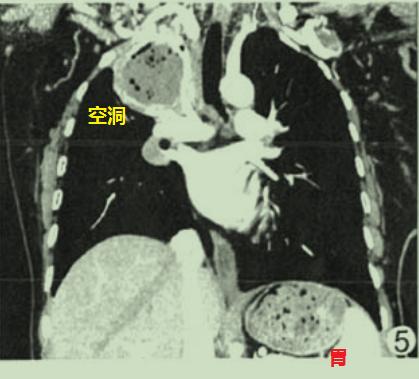

图3 放线菌感染图4也是肺部空洞悬浮气泡征,最终诊断也是肺部放线菌病。

图4 肺部空洞悬浮气泡征

图4 肺部空洞悬浮气泡征为什么肺放线菌病空洞内的空气会违反牛顿万有引力呢?有学者推测,对于肺放线菌病,空洞内低密度无强化的物质,其实是坏死组织+大量放线菌+硫磺颗粒,流动性差;空洞内的气体密度影,可能是含硫磺颗粒、放线菌的微脓肿,或是残存的扩张支气管。由此可见,空洞内的液体难以流动,气体也不容易流动,所以不会形成气液平。

不典型的肺部空洞悬浮气泡征

图6有学者认为也是肺部空洞悬浮气泡征,但并不典型。

图6 肺部空洞悬浮气泡征

图6 肺部空洞悬浮气泡征4